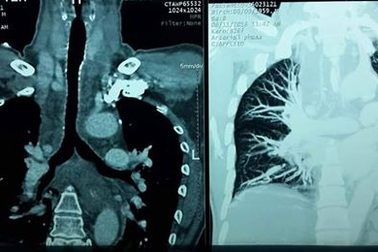

Chuyển bệnh nhân người Đài Loan nguy kịch về nước an toànBệnh nhân nam giới (57 tuổi, người Đài Loan) nhập viện Việt Đức và được chỉ định mổ cấp cứu áp xe trung thất. Tuy nhiên vì bệnh nhân không có người nhà ở Việt Nam, đã xin về nước điều trị. Bệnh nhân đã được hai bác sĩ Việt Nam đi theo chăm sóc trong hành trình và đã chuyển về nước an toàn.